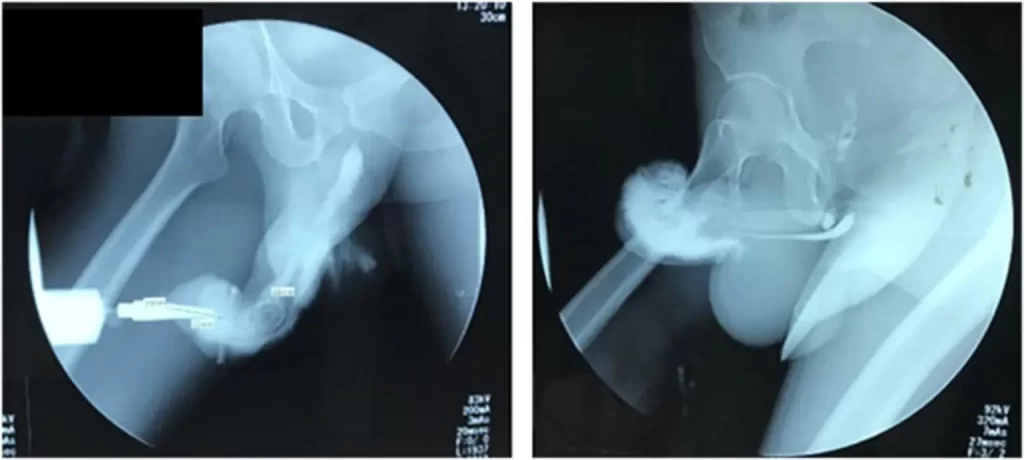

Ženy prý mají rádi zakřivené penisy, protože se pod speciálním úhlem dostanou k jejim skrytým erotogenním zónám. Pokud má muž penis až příliš zahnutý, může trpět Peyronieho nemocí. Při erekci dochází u takového muže k bolestem a také poruchám samotné erekce. Odhaduje se, že 7% mužské populace trpí touto nemocí. Nemoc lze medikamenty, případně chirurgicky léčit.